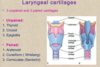

- skeleton of the larynx

- consists of 9 cartilages, three unpaired and three pair

- paired

- cuneiform cartilage

- arytenoid

- corniculate

- unpaired

- thyroid

- cricoid

- epiglottis

- laryngeal skeleton

- paired

- arytenoid

- cuneiform (wrisberg)

- corniculate (santorini)

- unpaired

- thyroid

- cricoid

- epiglottis

- thyroid cartilage

- forms the laryngeal prominence/ Adam’s appple in males

- consists of two laminae fused in the midline anteriorly

- forms bilateral cricothyroid jionts with the cricoid cartilage below, allowing the thyroid cartilage to tilt foward and backward on it

- cricoid cartilage

- is shaped like a signet ring with the broad lamina located posteriorly and the thinner arch in front

- articulates with the thyoid cartilage at bilateral cricothyroid joints

- is attached to it in the anterior midline at the cricothyroid ligament, where an emergency airway may be made

- cricothyrotomy

- epiglottic cartilage

- is attached to the hyoid bone and to the thyroid cartilage by ligaments

- is covered by mucous membran to form the epiglottis

- is pushed back and down over the laryngeal inlet (adults ) during swallowing to help prevent the enterance of food and drink

- artenoid cartilages

- are paired pyramidal-shaped carttilages that articulate with the superior border of cricoid cartilage lamina

- each has an apex

- muscular process and a coval process

- has the vocal ligament attached to itts vocal process anteriorly

- therefore, the vocal ligament attaches anteriorly to the thyroid cartilage and posteriorly to the aryttenoid cartilage

- are capable of three basic movements

- sliding toward or away from each other

- tilting anteriorly or posteriorly around a horizontal axis

- rotating around a vertical axis

- corniculate and cuneiform cartilages

- aren’t of exceptional importance but ar landmarks during laryngoscopy